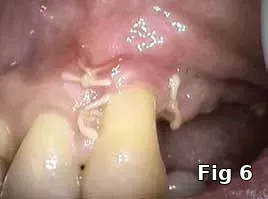

Flap closure management (Figs. 6–11): This patient is a 68-year-old female who has poorly controlled Type 2 Diabetis Melitus (DM) and is a one-pack-a-day smoker and refuses to not wear her partial denture during the primary soft-tissue healing phase (Fig. 6). In cases of possible delayed or compromised healing, using concentrated multifactorial growth factors at the site of injury (Fig. 7) prior to closure (Figs. 8–9) decreases those possibilities and improves and accelerates soft-tissue healing (Figs. 10–11) and diminishes the pain patients feel because of post operative inflammation.